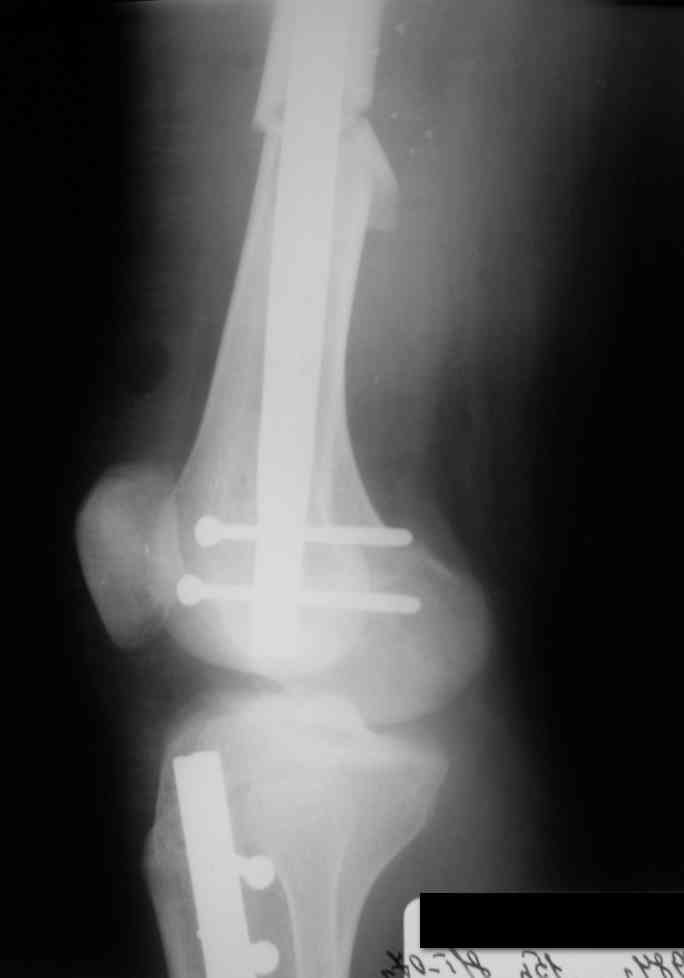

Вчера первый раз синтезировали голень гвоздем Fixion.

Спиральный оскольчатый перелом, ниже середины, у молодого парня. Сделали "классический" вариант гвоздя, который еще без винтов. Получилось все легко. Не торопясь, сделали операцию минут за 20. См. фото.

Дорогой Александр. Имею скромный опыт использования системы Fixion при переломах плеча, бедра и тибии. Всего 18 наблюдений с сентября 2006 г. Результаты отличные. Гвоздь индивидуален для каждого медуллярного канала. Легко имплантируется как в узкий, так и в деформированный канал. Это позволяет применять метод интрамедулярного остеосинтеза без ненужных потерь времени операции, флюороскопии и реально снижает крвопотерю и операционный риск. Удаление происходит без проблем. Особенно интересны больные с ипсилатеральными переломами бедра и голени.

В отношении ранней нагрузки при спиральных переломах лучше не торопиться. По данному случаю необходимо достигнуть исчезновения щели между штифтом и внутреним кортексом по Rg. А так картинка прекрасная - и длина сегмента и репозиция. Можно поздравить, коллега!